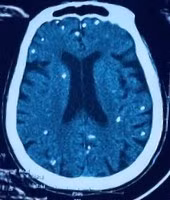

Người bệnh được chuyển lên từ tuyến trước vì rối loạn ý thức đe dọa suy hô hấp, hình ảnh cắt lớp vi tính sọ não và X-quang ngực cho thấy rất nhiều nốt cản quang trong nhu mô não và dưới da vùng ngực-bụng.

Nhiều nốt cản quang trong nhu mô não của người bệnh - Ảnh BVCC

Mặc dù xét nghiệm kháng thể IgM với sán dây lợn âm tính, các tổn thương trên X-quang gợi ý người bệnh trước đây bị nhiễm ấu trùng sán dây lợn, sau đó các nang sán trở nên vôi hóa và tồn tại lâu dài trong tổ chức. Người bệnh được điều trị theo phác đồ bệnh chính, đáp ứng và ra viện tiếp tục điều trị theo tuyến.